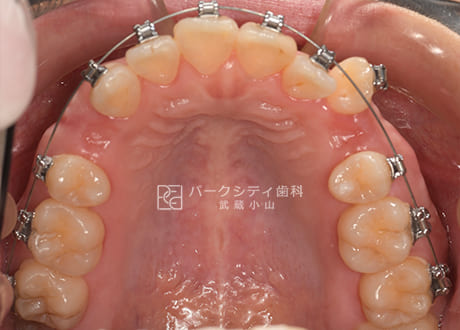

上顎術前

上顎術中